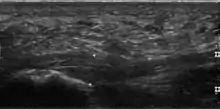

The plantar fascia has three fascicles-the central fascicle being the thickest at 4 mm, the lateral fascicle at 2 mm, and the medial less than a millimeter thick.[19] In theory, plantar fasciitis becomes more likely as the plantar fascia's thickness at the calcaneal insertion increases. A thickness of more than 4.5 mm ultrasound and 4 mm on MRI are useful for diagnosis.[20] Other imaging findings, such as thickening of the plantar aponeurosis, are nonspecific and have limited usefulness in diagnosing plantar fasciitis.[13]

Three-phase bone scan is a sensitive modality to detect active plantar fasciitis. Furthermore, a 3-phase bone scan can be used to monitor response to therapy, as demonstrated by decreased uptake after corticosteroid injections.[21]